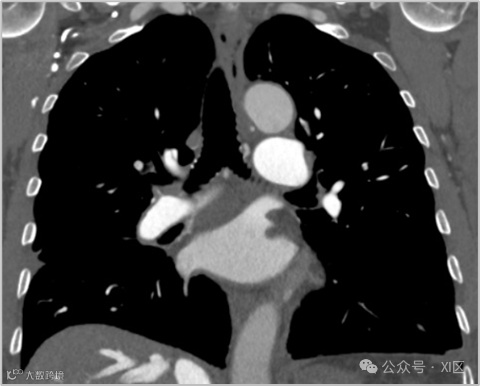

光子计数CT(PCCT)作为一种新兴CT技术,采用能量分辨的光子计数探测器(PCD),与传统的能量积分探测器(EID)相比,PCD能够识别不同能量的单个光子。PCCT具有提高空间分辨率、减少噪声、增强对比度并降低辐射剂量的潜力,还允许使用替代对比剂。在一项临床研究中,PCCT在图像质量和辐射剂量方面优于传统的192排双能量CT(EID)扫描仪(1.4 mSv vs. 3.3 mSv),并减少了对比剂的用量。未来需进一步的前瞻性研究来验证PCCT的潜力。(更多关于PCCT的内容参见XI区:光子计数CT丨发展简史,物理原理与临床优势)

慢性血栓栓塞性肺动脉高压(CTEPH)PCCT成像